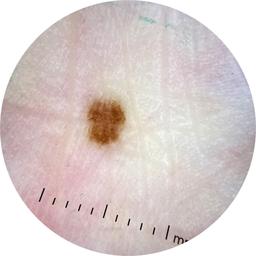

ISIC_6769723

Information

2013 x 2013

Clinical

Field Value

acquisition_day 298

age_approx 45

anatom_site_1 Lower extremity

anatom_site_general lower extremity

concomitant_biopsy False

diagnosis_1 Benign

diagnosis_confirm_type single image expert consensus

family_hx_mm True

fitzpatrick_skin_type I

image_manipulation instrument only

image_type dermoscopic

lesion_id IL_0892257

patient_id IP_5324562

personal_hx_mm True

sex female